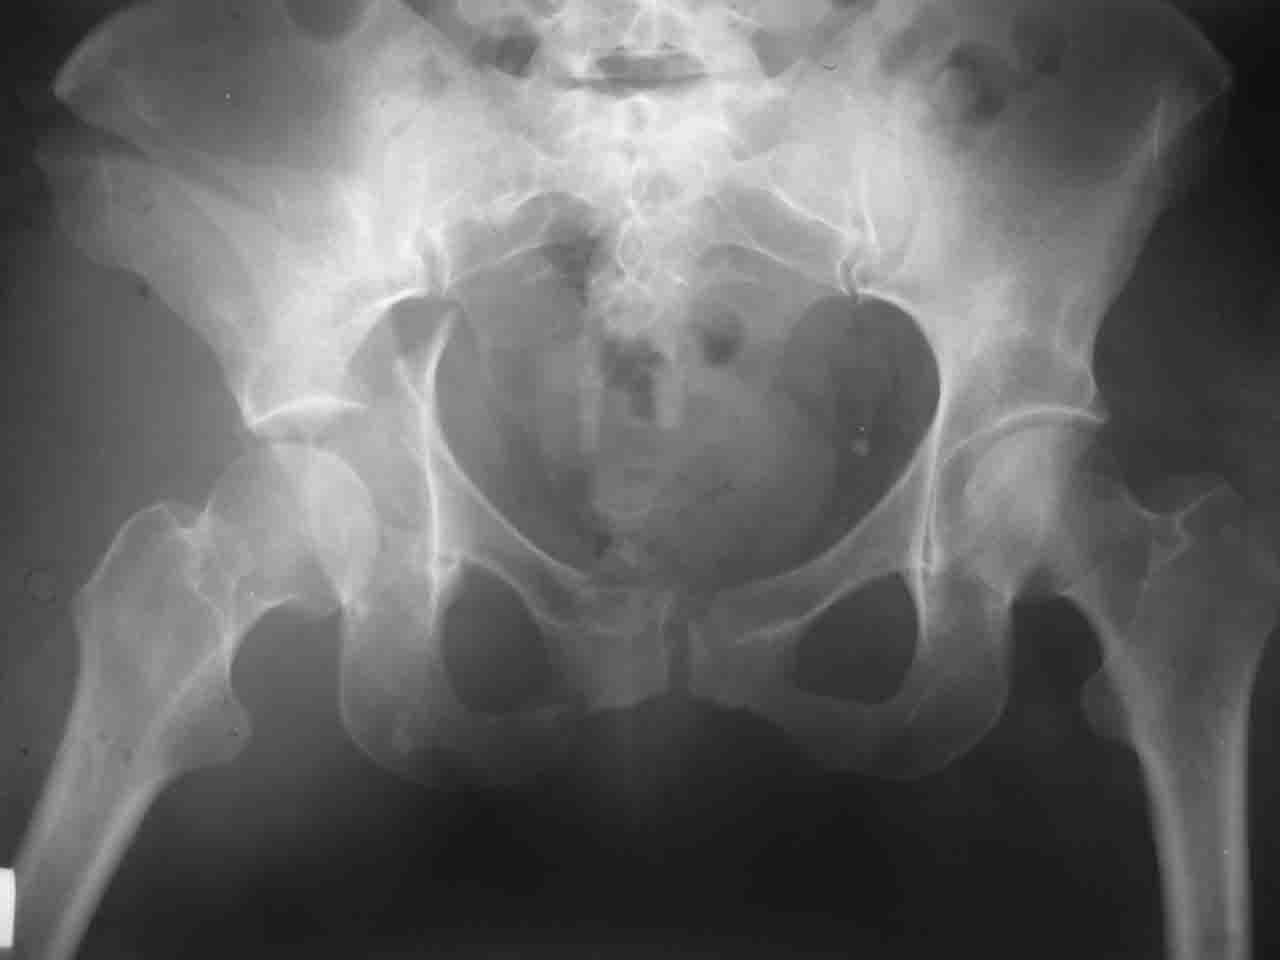

А какой отдел вертлужной впадины более важен передний или задний? Чем был обусловлен выбор доступа к суставу? Проще говоря, почему вы пошли передним доступом на двухколонный перелом? Мне понятны ваши сомнения, когда не удется сделать все что хотелось бы. В данном случае доступ должен быть чрезвертельным боковым (как и советовал Рунков) или двумя доступами.

> А какой отдел вертлужной впадины более важен - передний или задний?

Однозначного ответа у меня нет : лучше быть богатым и здоровым , чем бедным и больным :-))

Логика подсказывает, что все-таки лучше иметь анатомически полноценную впадину, хотя ранее упоминалось состояние вторичной конгруэнтности и одно наблюдение у меня есть, когда у больного с полностью нарушенной анатомией впадины и подвывихом головки бедра кзади и кверху боли отсутствовали при относительно достаточном для стиля жизни больного объёме движений. Но это только одно наблюдение и кроме перелома впадины у этогобольного была и тяжелая ЧМТ в анамнезе. Основываясь на формулировке структуры ацетабулюм Э. Летурнеля - как перевернутой буквы Y, впадина для полноценной функции сустава должна иметь сферичность, соответствующую размеру головки бедра и если один из компонентов в дефиците, то функциональные последствия рано или поздно проявятся.

Вопрос доступа к вертлужной впадине при остеосинтезе задача не простая. Конечно, у Летурнеля и Тайла всё давно описано, нам остается только брать на вооружение. Но сами понимаете, что не бывает двух одинаковых ситуаций, поэтому в каждом случае вопрос решается сугубо индивидуально. Наша главная цель - восстановить анатомию с нанесением минимальной дополнительной травмы тазобедреннному суставу, думаю с этим никто не поспорит. Расширенный илиофеморальный доступ уж слишком травматичен (как сказал один коллега "таз лежит отдельно, больной отдельно").Стоит ли делать из пациента анатомический препарат для того чтобы легче ориентироваться. Да и нужно ли собирать всю "мозаику"? Мы применяли при таких операциях своеобразную операционную хитрость - сначала устраняли грубое смещение крыла под гребнем с фиксацией так называемой "плавающей" пластиной (временно фиксированной на двух винтах)- доступ или продлевали боковой, или делали небольшой дополнительный разрез над гребнем. Это позволяло устранить грубое смещение и захождение отломков тела повздошной кости, что значительно облегчало репозицию и остеосинтез впадины над сводом. Основное внимание конечно же уделяли нагружаемому задне-верхнему отделу. Сообщите ваш адрес, пришлю схемы и рентгенограммы.